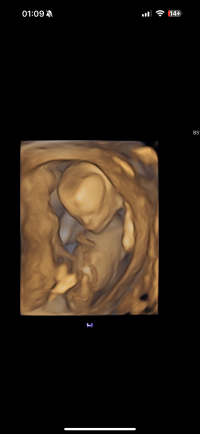

Kan se ut som jente, men veldig vanskelig å se på bildeneNoen som vil gjette kjønn? Uke 14+2